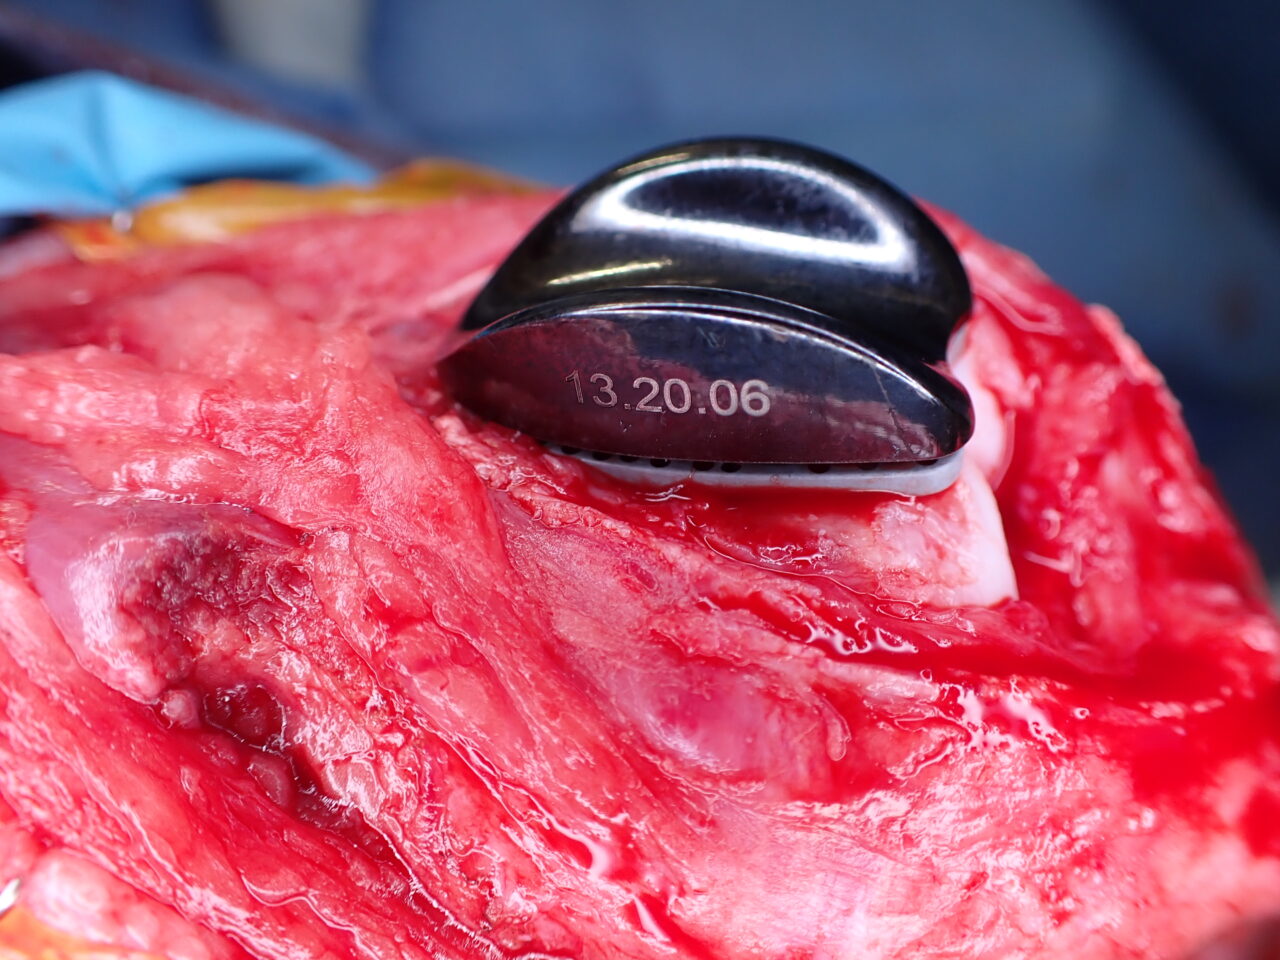

膝蓋骨内方脱臼に伴い慢性の異常な刺激が進行し、骨関節炎を認め関節軟骨はすでに不可逆的な変性を呈しています。多くの外科手術は”整復”を目的としますが、関節炎が進行した関節においては、単なる整復だけでは痛みや機能障害は残り続けます。そこで必要な手技は”再建”です。損傷した関節面をそのまま使うのではなく、人工滑車(PGR)を用いて新たな滑走面(DLC)を構築することで、関節内の異常なストレスを減少させ、除痛と機能回復を図ります。HAコーティングのベースプレートと骨がオッセオ・インテグレーションを起こすまでは安静が必要です。